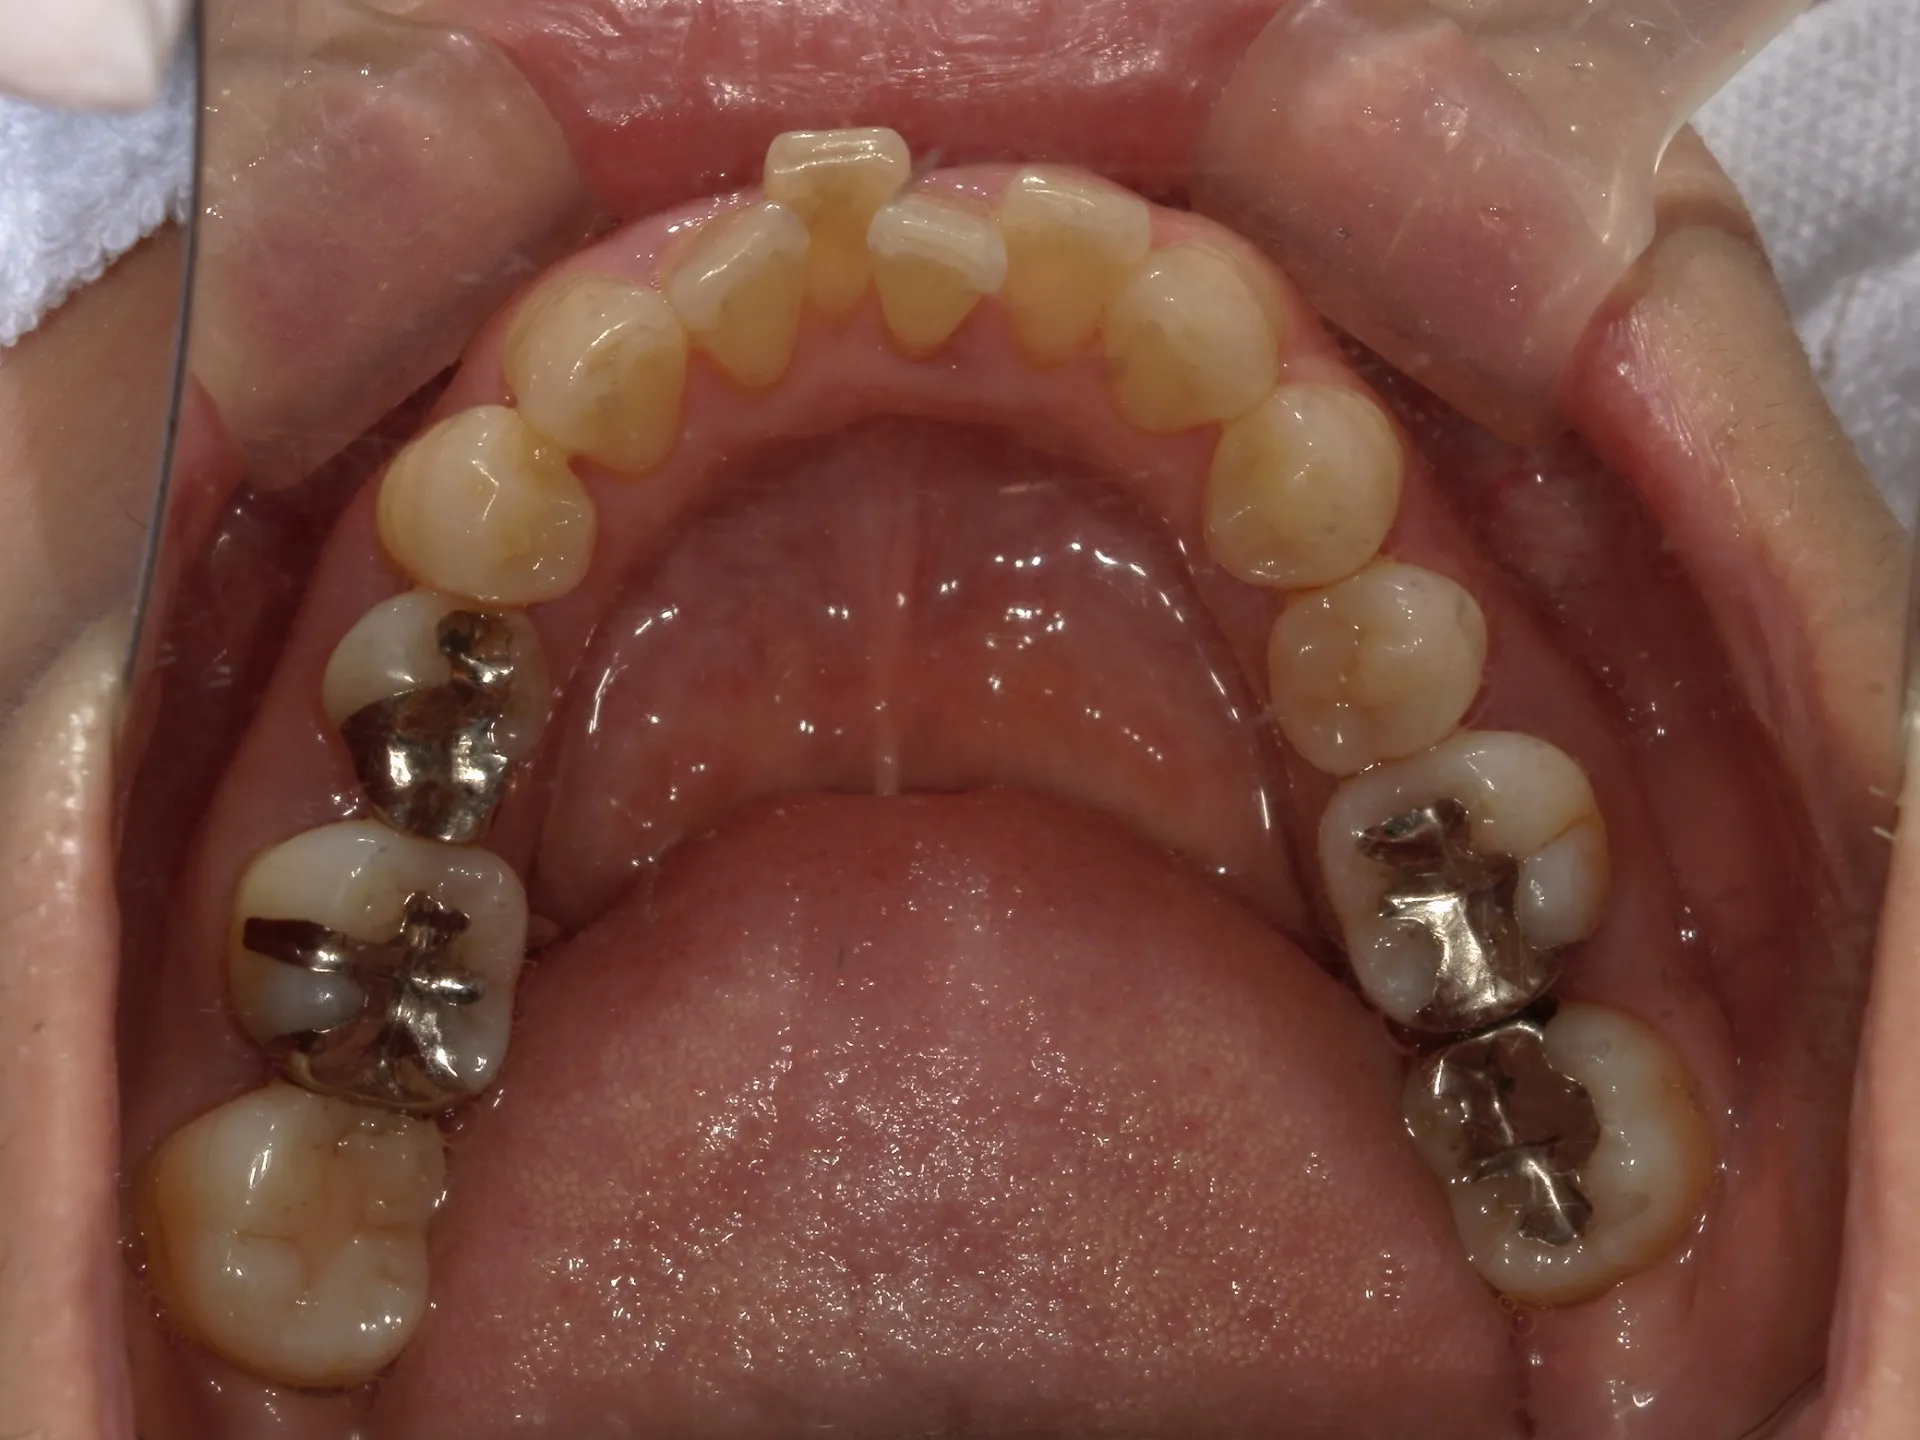

当院では矯正治療と歯周治療を平行して行うことにより矯正治療を進めていけることができました。

しかしながら、今回の治療途中で歯茎が腫れるなどの影響もあり、歯周治療中の矯正治療はリスクであることは患者様にも初回の段階で説明していることもあり、患者様もこの状態の歯並びで満足しており、歯を残すためにも今回は矯正治療を中断する希望をされました。